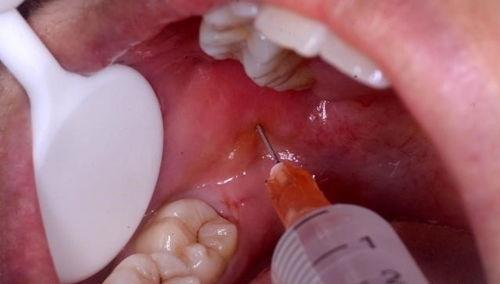

别急,让我带你一探究竟。在拔智齿的视频中,你可以看到医生们是如何使用专业的工具,小心翼翼地分离智齿与牙槽骨的连接。他们会用牙挺、牙钳等工具,将智齿从牙槽骨中拔出。整个过程看似简单,但实际上需要医生们丰富的经验和精湛的技艺。